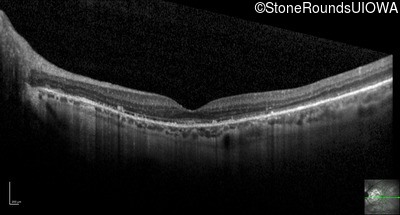

Optical Coherence Tomography - Left - 20/25 +3

Exemplar / OCT Stack

OCT Stack